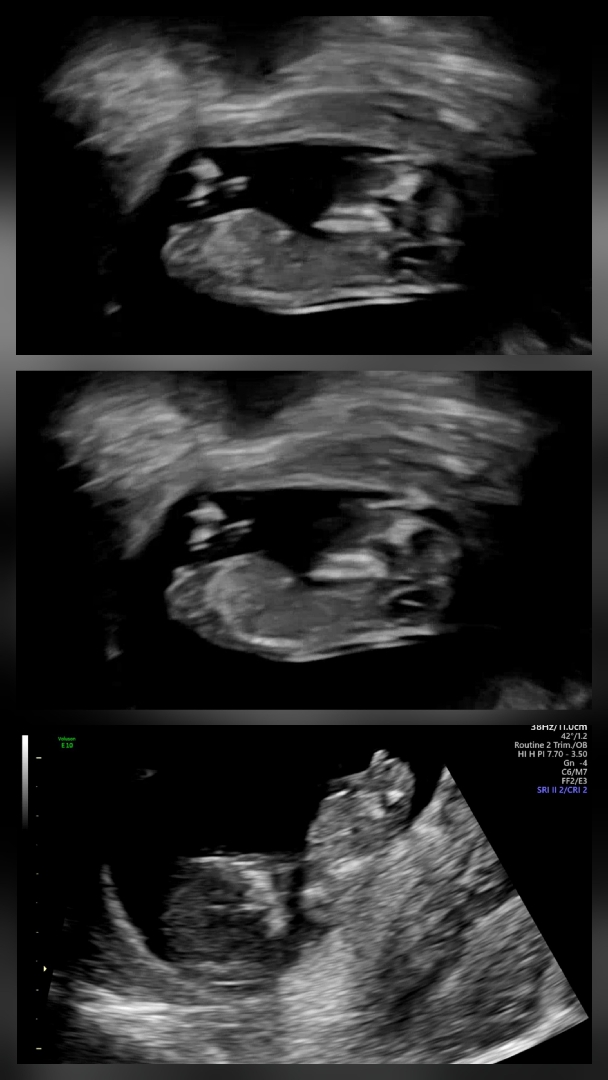

12주1일 저도 각도법 한번만 봐주세요~

오늘 예정일이 당겨지면서 12주 1일이 되었고 1차 기형아 검사를 하게됐는데 아들인지 딸인지 헷갈리네요ㅎㅎ 어때 보이나요? 의견부탁드려요